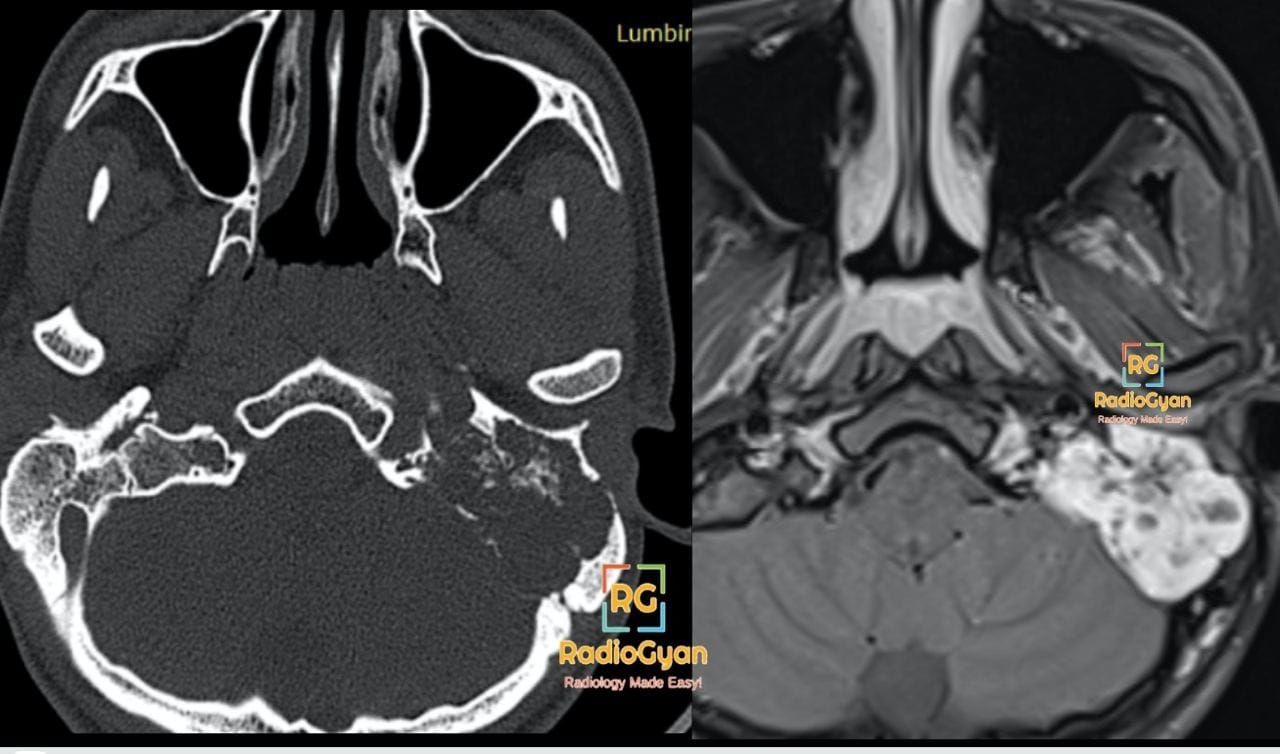

This is an axial computed tomography (CT) scan and an axial magnetic resonance imaging (MRI) scan of the skull base, demonstrating a Left Glomus Jugulare Paraganglioma. The CT scan on the left shows bone erosion and destruction involving the left jugular foramen. The MRI on the right reveals a brightly enhancing, lobulated mass in the same region, consistent with the diagnosis.

- CT: Lobulated soft tissue mass in left jugular foramen with intense post-contrast enhancement; bone erosion and destruction of adjacent skull base including jugular foramen; no middle ear involvement

- MRI: T1 iso- to hypointense lobulated mass with โsalt-and-pepperโ appearance due to flow voids and hemorrhage; T2 hyperintense with multiple punctate flow voids; intense homogeneous or heterogeneous enhancement post-gadolinium

- Signs: “Salt-and-pepper” appearance on MRI due to slow flow/high vascularity; jugular foramen erosion on CT as a classic sign of glomus jugulare tumor